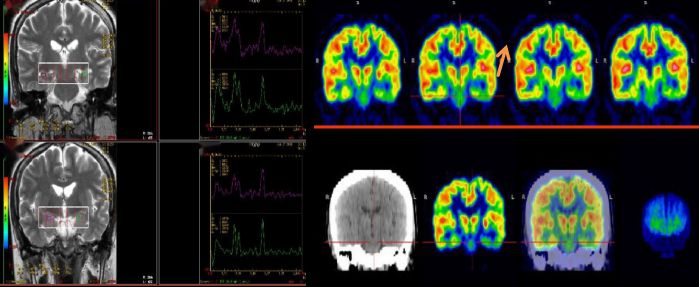

25歲,男,癲癇反復(fù)發(fā)作 MRS:雙側(cè)海馬區(qū)NAA降低,提示:神經(jīng)元缺失;PET顯像提示:左側(cè)顳葉代謝減低,手術(shù)切除,術(shù)后病理提示符合局部腦組織缺氧病理改變,術(shù)后患者明顯好轉(zhuǎn)。